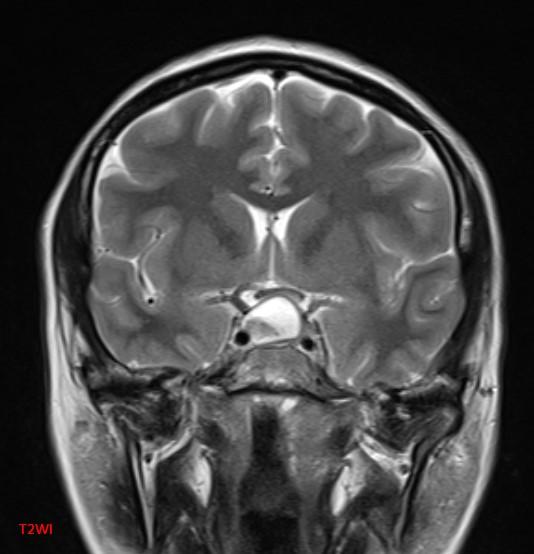

*30-year-old pregnant woman with headache and diplopia.

What is the most likely diagnosis?

Answer: Pituitary apoplexy

MR images reveal an ovoid lesion (red arrows) in the pituitary fossa with suprasellar extension. The optic chiasm is compressed (yellow arrows). The lesion is T1 and T2 hyperintense showing blood-blood fluid level (blue arrows).